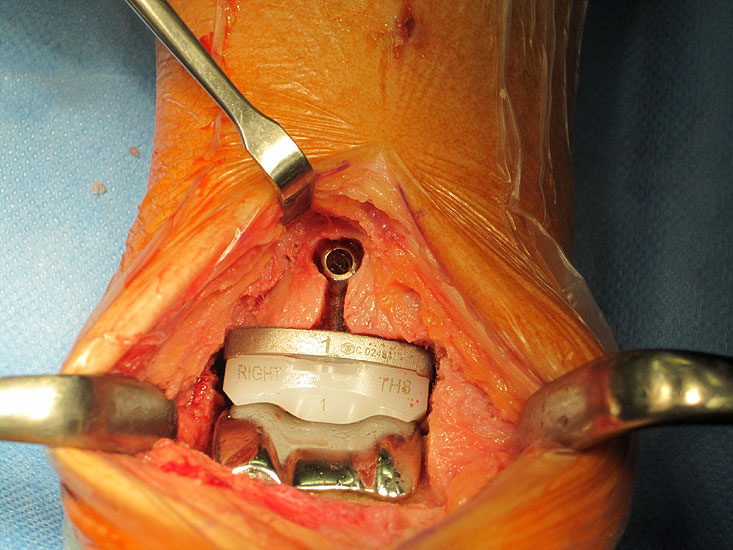

Osteosynthese eines intraoperativ frakturierten medialen Malleolus mit perkutanen Schrauben.

Abbildung 19

1. intraoperative Innenknöchelfraktur:

Mögliche Ursachen können eine zu weit medial plazierte Tibiakomponente oder eine zu weit mediale, nicht nach lateral konvergierende Sägerichtung im Rahmen der ventrodorsalen distalen Tibiaresektion sein (Abb. 19).